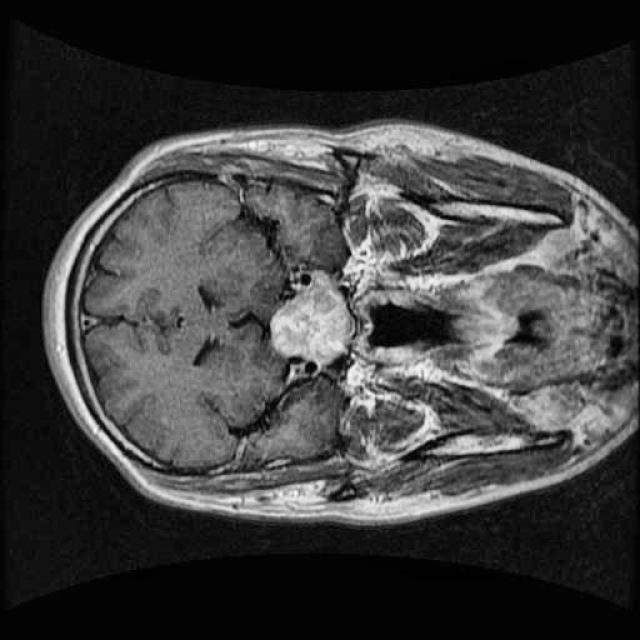

In this demo, we will build our first segmentation model using OneAI. Unlike classification or object detection, segmentation assigns a class label to every individual pixel of an image. This makes it particularly well suited for medical imaging tasks, such as identifying tumor regions in MRI scans.

The goal of this tutorial is to demonstrate how a brain tumor segmentation model can be trained using only 50 MRI images. The focus is not on achieving state-of-the-art medical performance, but on showing how quickly and efficiently a segmentation workflow can be set up and trained with OneAI.

For this tutorial, we use a small dataset consisting of 50 MRI images of the human brain.

These images were selected from a larger Roboflow dataset containing many more samples annotated in an object detection format. You can find the original dataset here.

Even with a relatively small dataset, segmentation combined with targeted augmentations can extract useful spatial information and allow us to train a functional model.